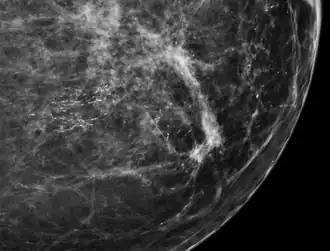

Microcalcifications are tiny deposits of calcium salts that are too small to be felt but can be detected by imaging.[1]

They can be scattered throughout the mammary gland, or occur in clusters. Microcalcifications can be an early sign of breast cancer. Based on morphology, it is possible to classify by radiography how likely microcalcifications are to indicate cancer. [2]